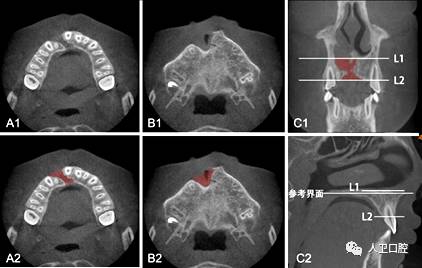

图5-2-12  参考层面的标志点

A1、A2.水平位及冠状位显示分别为左侧腭大孔中外缘(点①)  B1、B2.水平位及冠状位显示右侧腭大孔中外缘(点②)  C1、C2.水平位及矢状位显示前鼻棘点(点③)